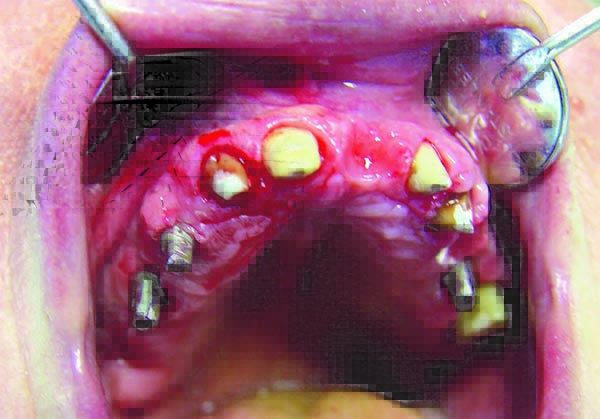

Another clinical case from my practice.

A physical CAD/CAM plastic model of the mandibula with a planned and sketched total SPI. The arrow indicates the presence of two available interosseous implants, which are suitable to be used to support the dental bridge and are not an obstacle for the new SPI.

View from the right

![/userfiles/files/kniga46.jpg [/userfiles/files/kniga46.jpg]](/userfiles/files/kniga46.jpg)

A view from the left. The places with the marked openings for the fixing screws can be clearly seen on both pictures.

While the required number of screws for the partial SPI is 2, the number for the total mandibular SPI screws is 4, and for the maxilla – 5 or 6.